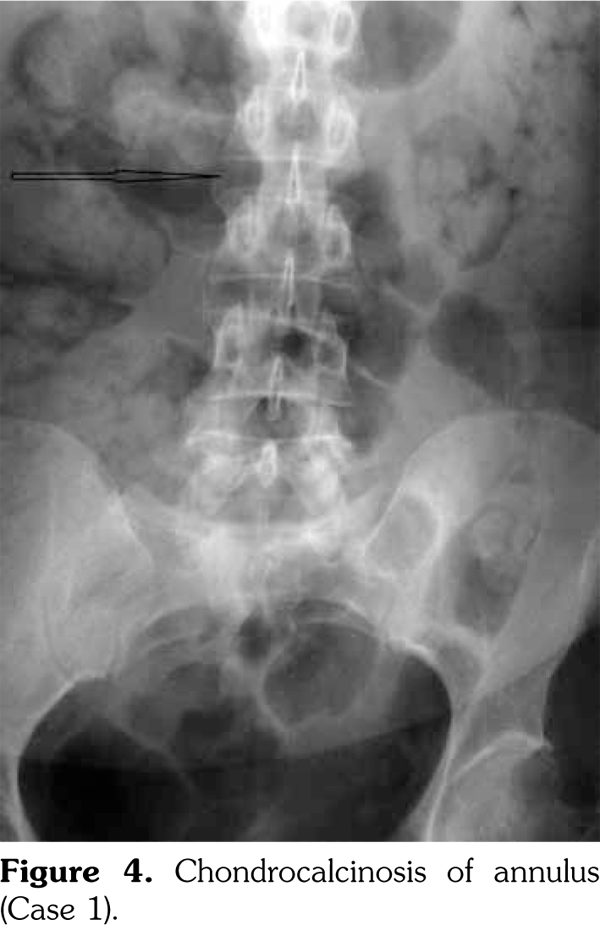

On examination, there was swelling and painful restriction of movement in her right knee. Imaging revealed calcification of cartilage of wrists, knee joints and hip joints although no microscopic confirmation was possible at this stage (Figure 1-4). She was investigated for a possible cause for CC, although investigations to screen for a metabolic cause turned out to be negative with a possibility for hereditary CC.

Case 1- A 35-year-old female patient was admitted to the hospital with an episode of community acquired pneumonia. During her stay at the hospital, she developed a right knee joint pain and an effusion. Joint sepsis was excluded by an orthopedic surgeon. However, during her stay, she complained of pain in both knees and wrist joints needing a rheumatology consultation.

An acute episode of CPPD disease may occur spontaneously or develop after trauma, surgery or a severe medical illness, similar to an attack of gout. Knee is the most commonly involved joint, followed by the wrist, metacarpophalangeal, hips, shoulder, and ankle joints.(10) It is polyarticular in approximately two-thirds of patients, and often occurs in an asymmetric pattern.(11) Rarely, there may be deposition of CPPD crystals in other parts of the skeleton, e.g. in the spine, symphysis pubis or temporomandibular joint.(9) CPPD can also be associated with tendinitis, tenosynovitis and bursitis.(8,12)